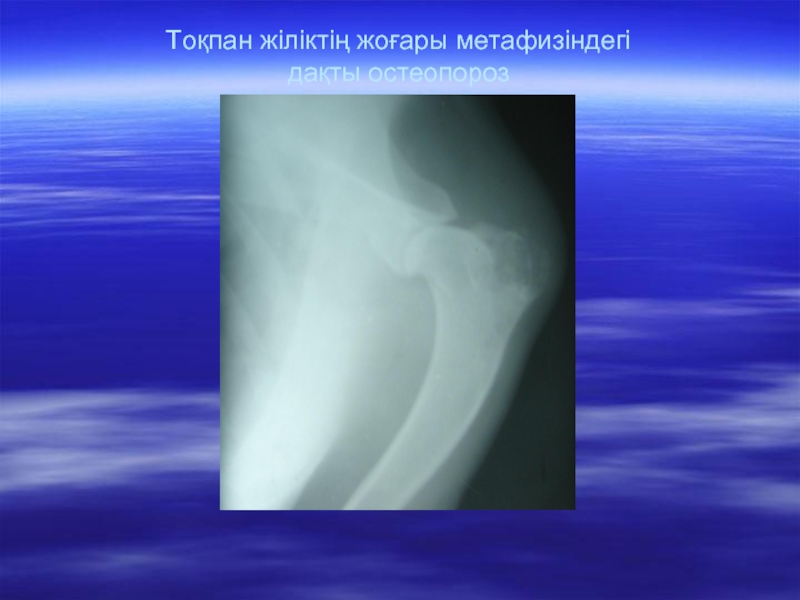

Слайд 16Остеопороз. Сүйек торшаларының ыдырау құбылысының, оның түзілу (жаңару) құбылысынан басым болуы.

Сүйек торшалары және олардағы минералды заттар азаяды, соның салдарынан сүйек рентген сәулесін аз ұстайды. Сүйек кестелері үлкейеді, тығыз қабаты жұқарады, жіліктің майы тұратын қуыс кеңейеді. Сүйектің шеттері тығыздалып, жұқарып анық көрінеді. Бірақ сүйек өзінің алғашқы пішінін, түрін сақтап қалады.

Слайд 17Тоқпан жіліктің жоғары метафизіндегі дақты остеопороз